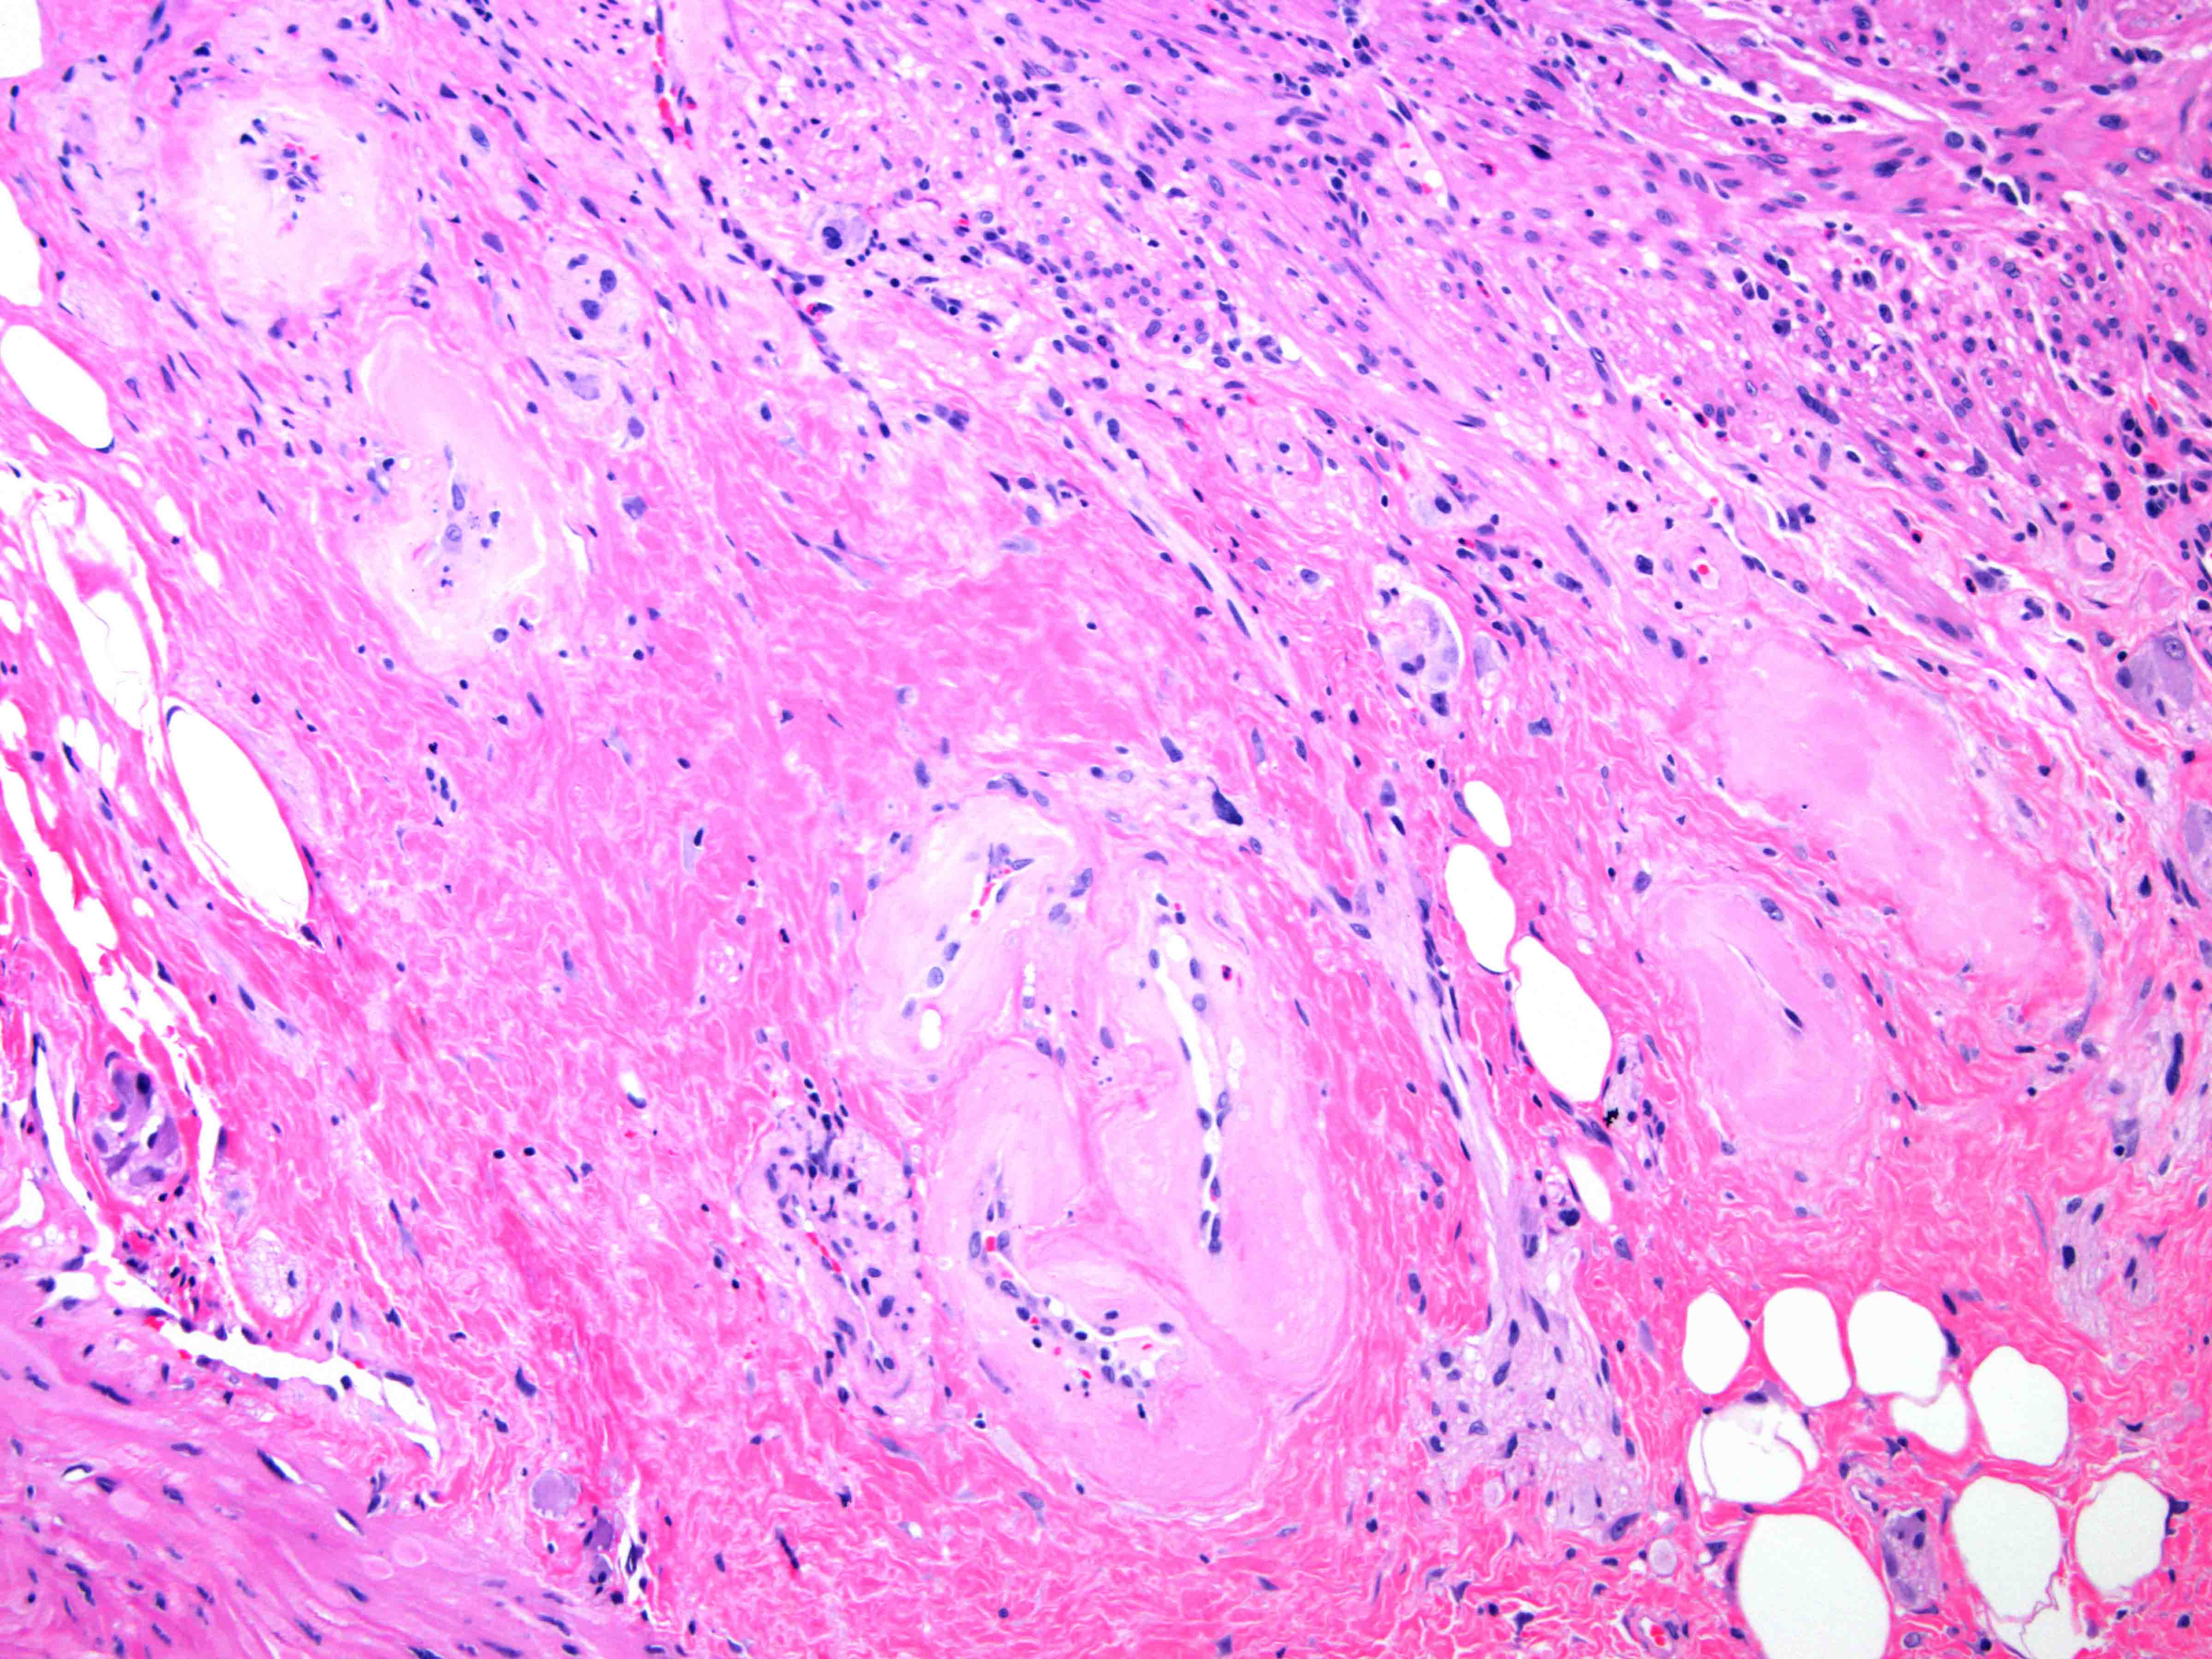

Microscopic (histologic) images

- Submucosa and deeper layers:

- Vasculature

- Hyalinization and fibrosis of vessel wall

- Intimal thickening

- Vascular ectasia or narrowing

- Thrombosis

- Endothelial cell atypia

- Vasculature

- Colonic mucosa with lamina propria fibrosis and ectatic, hyalinized vessels consistent with mild chronic radiation associated colitis

E. Radiation colitis, chronic. Chronic radiation colitis is expected at > 6 months postradiation therapy. Sections show ulcerations, mild epithelial atypia, architectural changes and atrophy. The lamina propria contains fibrosis, mild chronic inflammation and fibroblast atypia (enlarged hyperchromatic nuclei). The vasculature within submucosal and deeper layers contains hyalinization of vessel wall and intimal thickening. Vascular ectasia, narrowing and thrombosis can also be present. Collagenous colitis (answer A) typically presents with history of watery diarrhea and a > 10 μM subepithelial collagen table (collagenous band). Infection (bacterial) (answer B) will present with an acute clinical history (example: diarrhea and vomiting) after an inciting event (example: food consumption, travel). Acute colitis and granulomas can sometimes be seen. Viral infections (example: cytomegalovirus, Epstein-Barr virus) can occur in immunocompromised patients (example: HIV or transplant) and will contain atypical cells with nuclear changes. Mucosal prolapse (answer C) can present endoscopically as a polyp and contains ingrowth of thick muscle bundles that can mechanically squeeze ensnared epithelium. This is accompanied by variable inflammation, ulceration and reaction epithelial change. Acute radiation colitis (answer D) is expected at < 6 months postradiation therapy. The inflammation is typically eosinophilic (characteristic) with eosinophilic cryptitis, crypt abscesses and lamina propria eosinophilia. Sections demonstrate reduced mitotic activity, apoptosis, reduced goblet cell mucin, goblet cell swelling, degenerative changes and atypia (nuclear enlargement and malorientation).